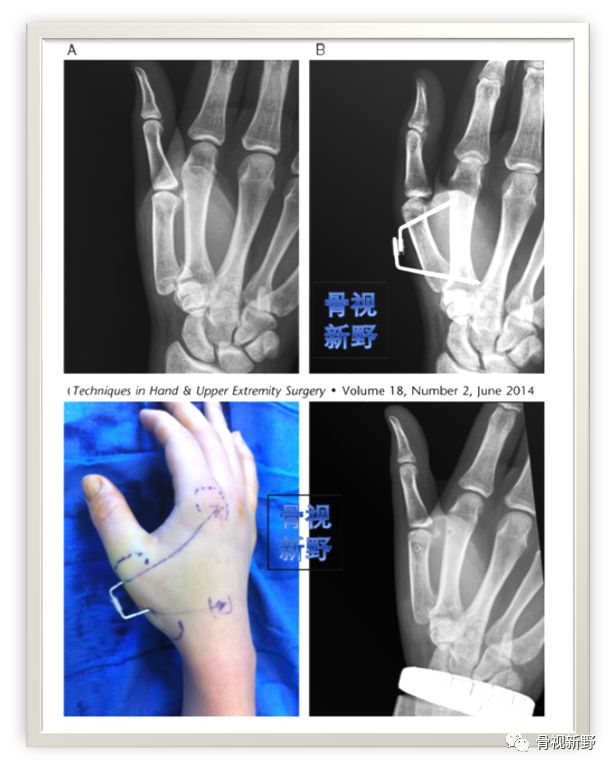

Mahmoud 等于2014年报道了切开复位、张力带内固定陈旧性Bennett骨折的创新术式。(示意图)

Case(ORIF with tension-band)

小切口张力带固定(河北三院  Xu Zhang,Xinzhong Shao et al.)